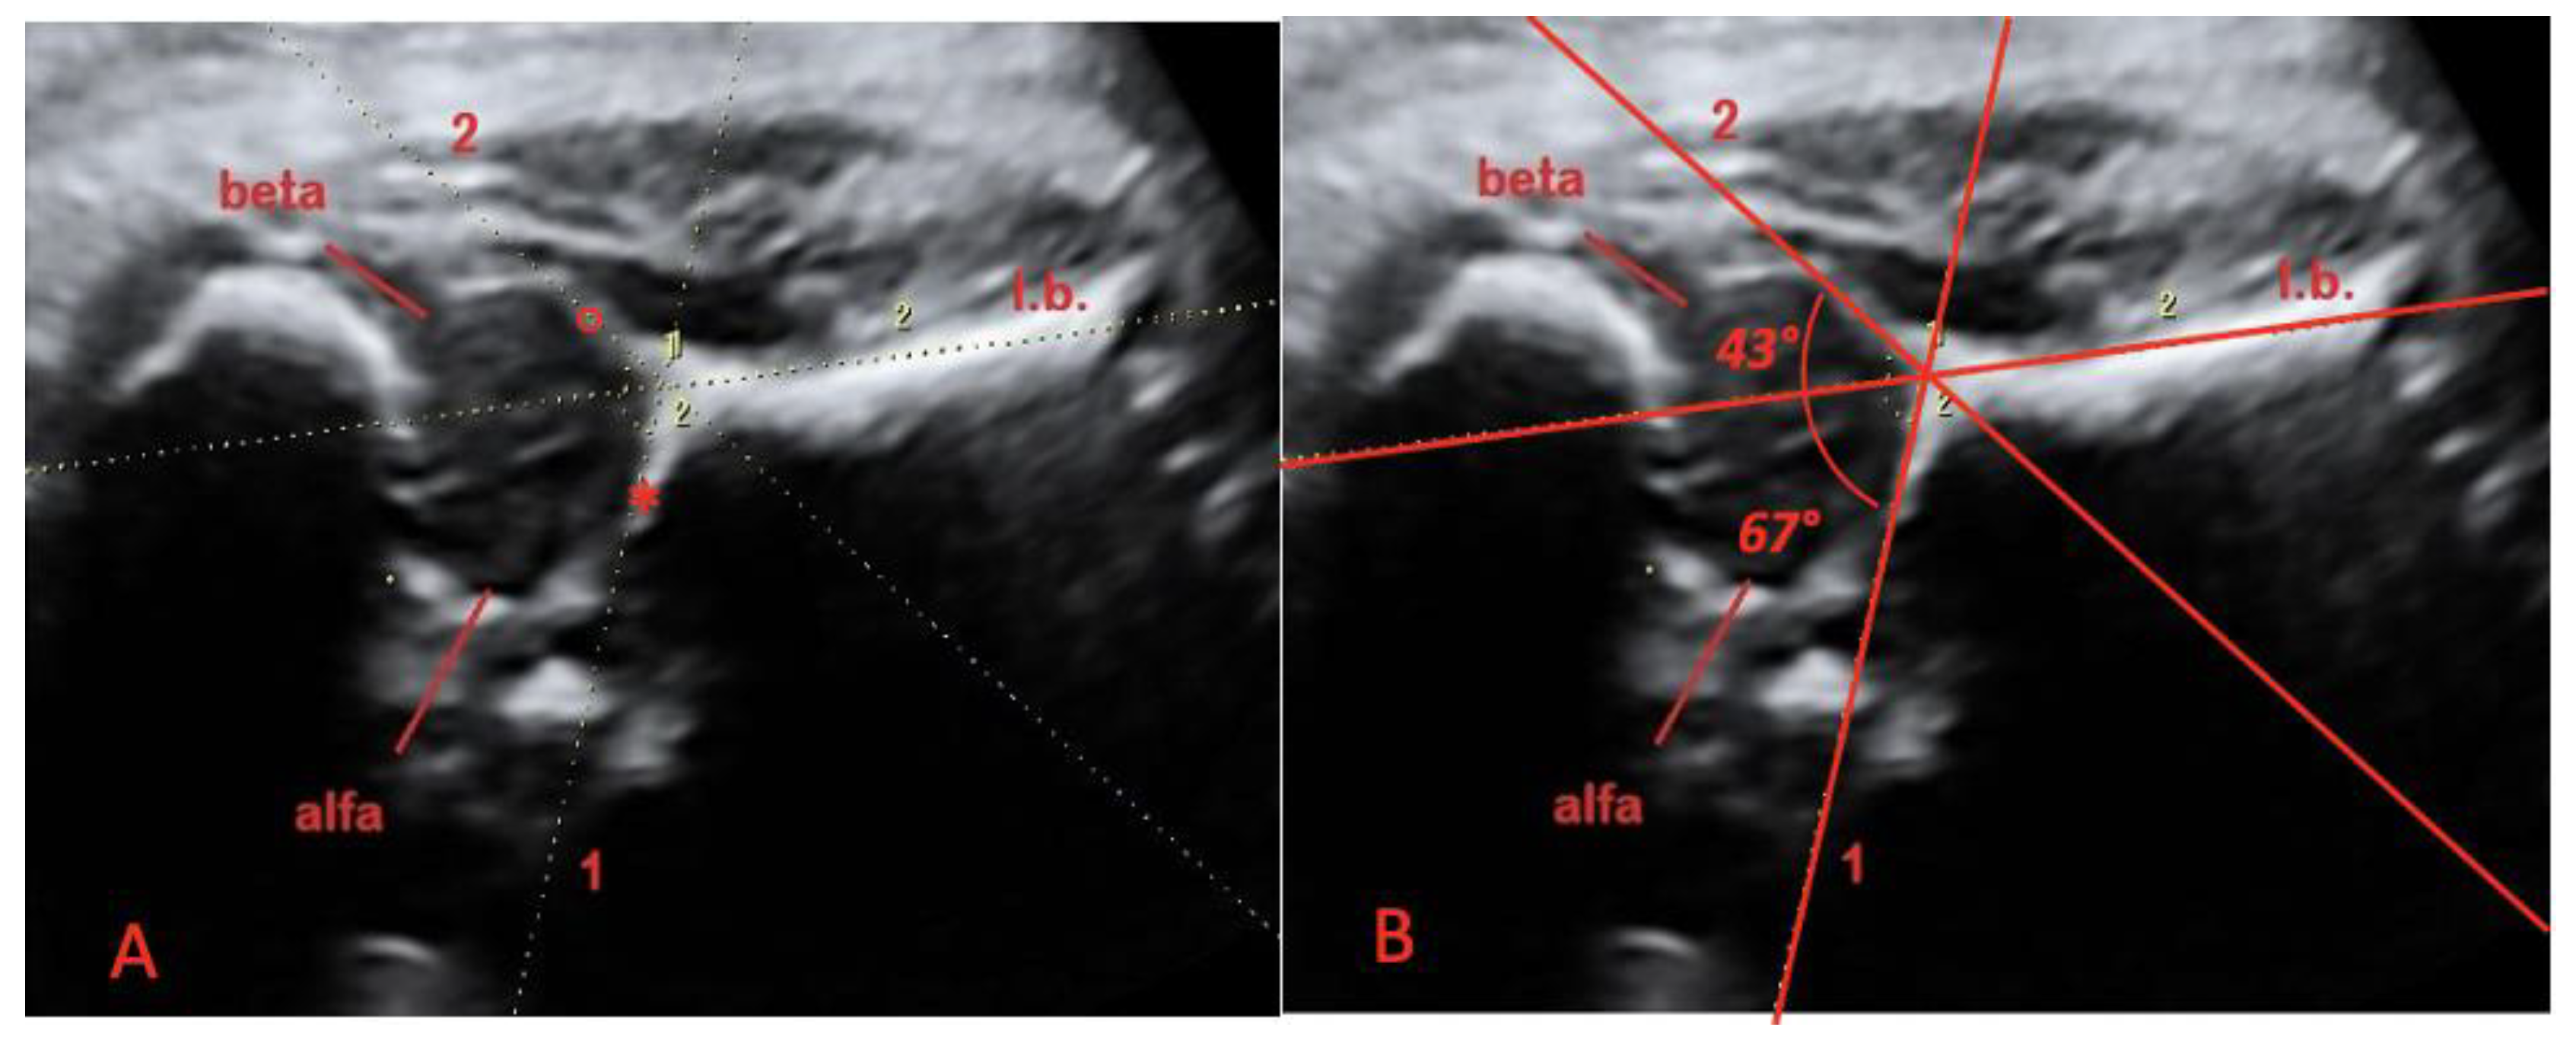

The starting plane for 3D insonation was the midsagittal plane of coxofemoral joint; the “Y” sign was then visualized (Figure 1). When it was possible, we acquired both coxofemoral articulations of the fetus; if it was not possible, only the more proximal articulation was acquired.

All examinations were performed by a single expert operator. The volume dataset of the coxofemoral articulation was acquired and then analyzed offline in the multiplanar mode by two operators (blinded to each other analysis) using the static volume contrast imaging (VCI) mode of the 4D view software (9.0 version, GE, Milan, Italy). The 3D image was adjusted to achieve the midsagittal view of the coxofemoral articulation in the A-plane (“Y sign”), with the reference dot positioned in the middle of the iliac bone, at the level of the sling opening. On the magnified A plane, the alpha and beta angles were calculated according to our modified Graf technique [15,16]. The alpha angle was defined as the angle formed by a line tangential to the horizontal iliac wing and a line tangential to bone roof (Figure 1); this is called the “bone angle”. The alpha angle was assumed as a measure at rest of the depth of the bony acetabulum. The beta angle was defined as the angle formed by a line tangential to the horizontal iliac wing and a line tangential to cartilaginous roof (Figure 1); this is called the “cartilage angle”. The beta angle was assumed as a quantitative measure at rest that that shows coverage of the femoral head by the cartilaginous acetabulum. Each angle was measured twice by two independent operators and for each of the above-mentioned measurements, and intra-observer and inter-observer reproducibility were calculated.

Figure 1. (A) Midsagittal plane of the coxofemoral joint, obtained with 3D ultrasound, in a fetus at 37 weeks of gestation: the “Y” sign. The iliac bone (I.b.), the labrum acetabular (°) and the lower edge of ossified ilium (*). (B) Midsagittal plane of coxofemoral joint, obtained with 3D ultrasound, in a fetus at 37 weeks of gestation: the “Y” sign. The alpha angle (“bone angle”) is the angle formed by a line tangential to the horizontal iliac wing (I.b.) and a line tangential to bone roof (*). The beta angle (“cartilage angle”) is the angle formed by a line tangential to the horizontal iliac wing (I.b.) and a line tangential to cartilaginous roof (°).